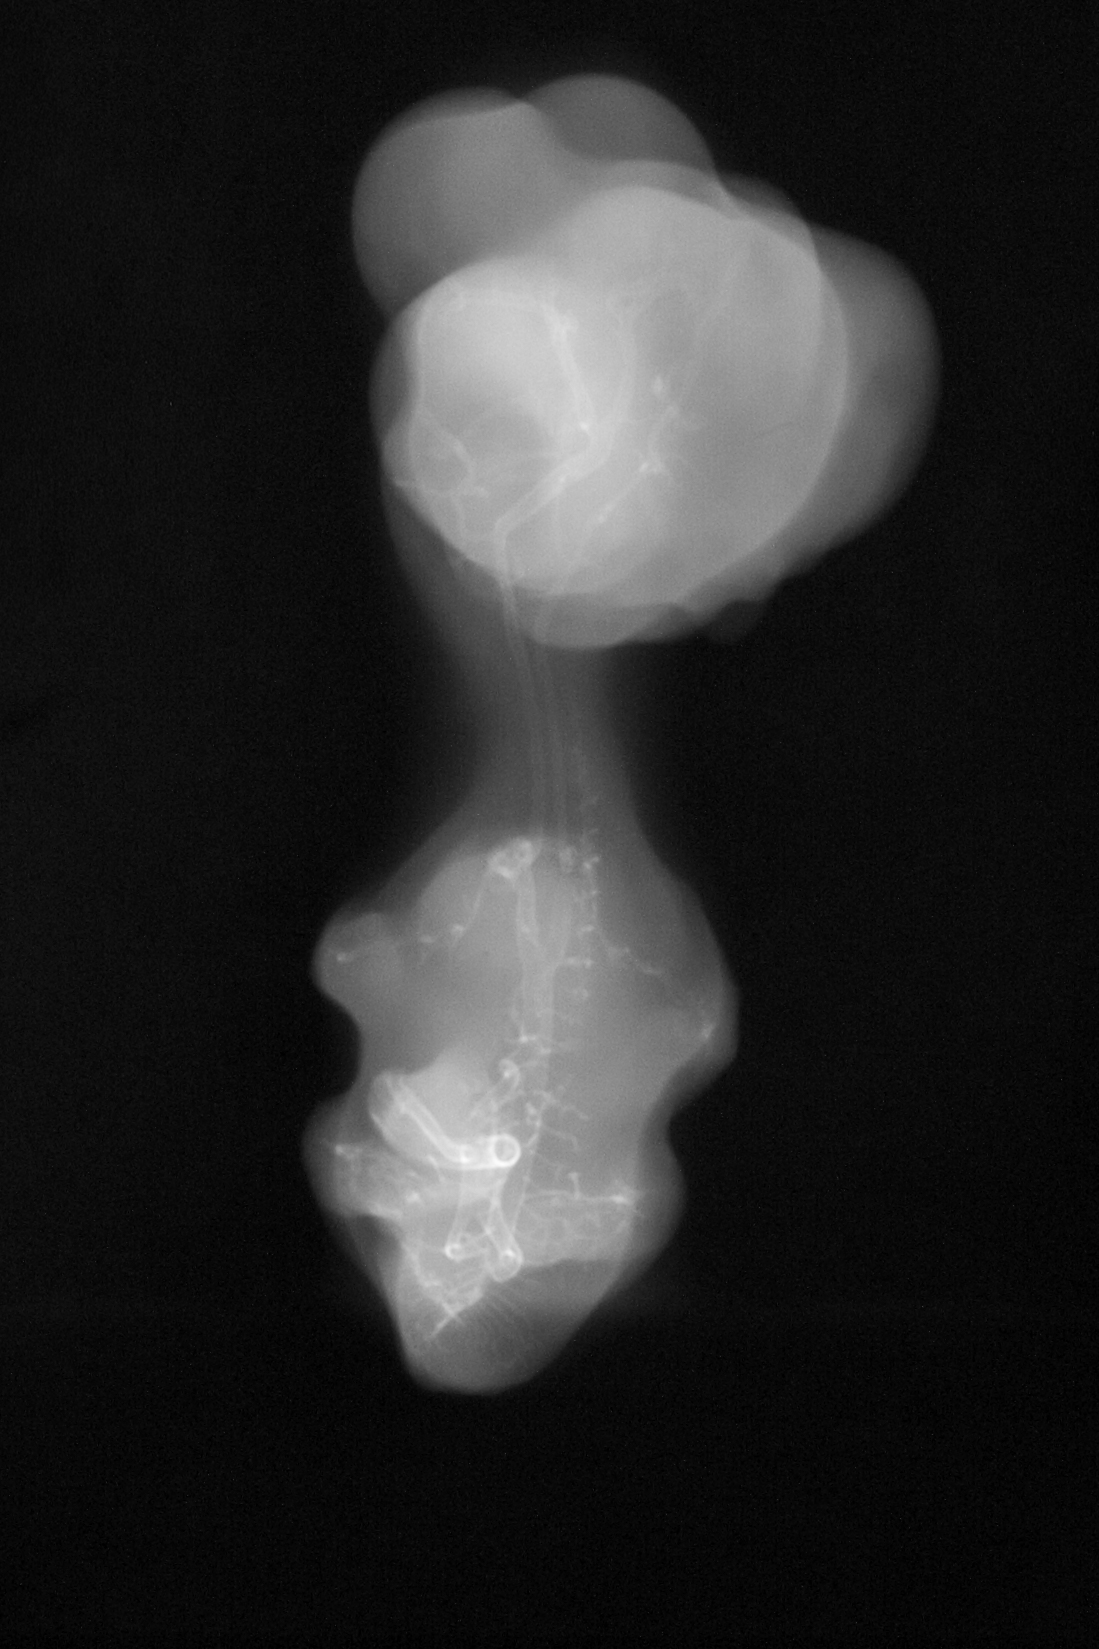

Chick Embryo Microangiography

Hamburger-Hamilton (HH) Stage 30 (approx. 6.5 days)

X-Ray Micrographs